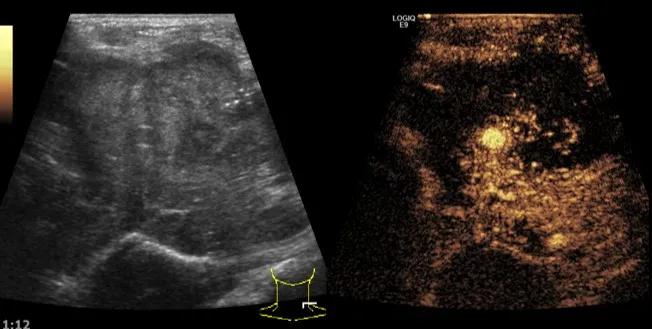

第二例是食管癌患者,术后半年余锁骨上固定淋巴结可触及肿大,疼痛非常明显,系统治疗后无缓解,患者希望通过局部处理缓解症状。造影显示强化信号明显,结节部分区域坏死,故主要针对强化区域从后向前的逐层的消融,皮下进行液体隔离减少烫伤。热消融后影像显示血流增强消失,弹性、硬度增高,一个月后复查显示充盈缺损,完全消融,疗效远超预期。

(病例2图例)